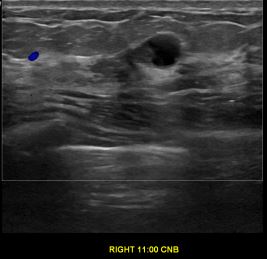

상기환자는 외부검사상 조직검사 권유받고 내원하신 40대 중반

여성분으로 의심스러운 우측유방혹 조직검사 시행해 제자리암으로 진단되었습니다